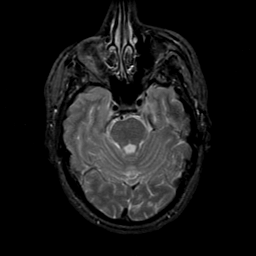

MR Study #21, November 3, 1991 -- Slice #15